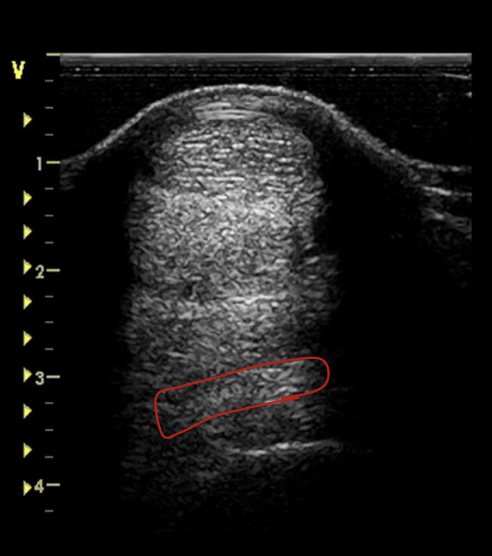

what is the red circling?

suspensory ligament at proximal MC 3